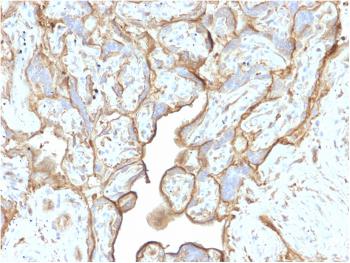

Anti-BG8 LewisY Monoclonal Antibody (Clone:IHC517)

Figure 1: Immunohistochemical analysis of BG8, Lewisy (IHC517) on Thyroid Cancer

BG8 LewisY, also known as LewisY blood antigen or simply BG8, is a blood group antigen that has been identified in many studies as a potential marker for differentiation between pulmonary adenocarcinoma (PACA) and epithelioid mesothelioma (EM). It has been reported that sensitivity of non-mesothelial antigens for adenocarcinoma is organ-dependent. When attempting to differentiate epithelioid mesothelioma from adenocarcinoma, BG8 LewisY performed at a sensitivity of 98% in the breast cancer group, and 100% in the lung cancer group.

Recommended dilutions: Immunohistochemical analysis: 1:100 - 1:200. However, this need to be optimized based on the research applications.